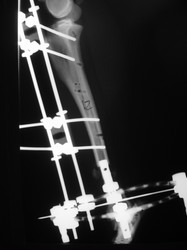

PRÁCTICAS CURSO DE FIJACIÓN EXTERNA PERFECCIONAMIENTO.

Híbrido.